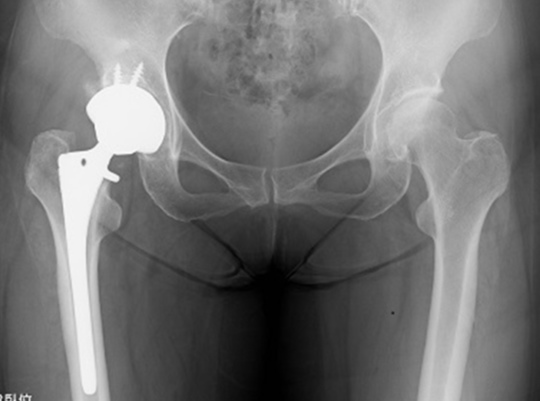

繰り返される股関節痛の最終形態がOPE

まず最初に、「骨の変形は手術以外は絶対に変えられない!」ということを前提にありますが、

先ほども記載しましたが、ヒトのカラダは1回 悪くなったものを変える方法は手術しかありません。

しかし、いかに「手術しない! 手術させない!」ためには、腰椎・骨盤・股関節の機能を修正すること!

股関節が変形しているということは、若い時からのカラダの機能不全を放置した結果、股関節に負荷がかかり変形としてカラダに現れている。